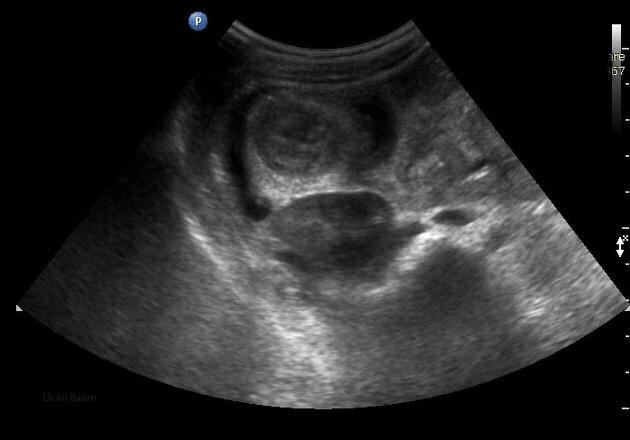

La invaginación intestinal es la causa más común de obstrucción intestinal en niños de 3 meses a 3 años. Se caracteriza porque un segmento de intestino penetra en otro segmento intestinal. Puede presentarse...